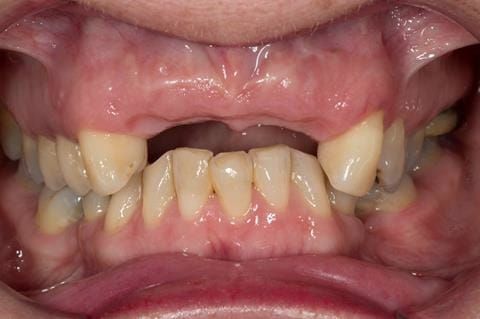

- High smile line showing gum above gingival zeniths of upper front teeth when smiling. Aesthetic failure of the upper four incisors with inflammation of the gingivae and mis-match of the gingival zenith levels.

- Other than the maxillary incisors the remaining dentition was in marginally better condition being moderately to heavily restored. Many will probably require replacement and restoration from time to time mainly from wear and tear owing to occlusal forces.

Following consultation and second discussion appointment the patient chose to have option 3 namely, a maxillary cobalt chromium based partial denture/protective occlusal splint. The clinical situation and treatment process is shown in detail below with photographs. The patient was successfully rehabilitated with this and her quality of life considerably improved. The clinical work was provided by Finlay and the technical work by Rowan.